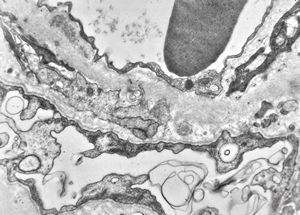

F,14y. | Alport syndrome - split and laminated, thick/thin basement membranes